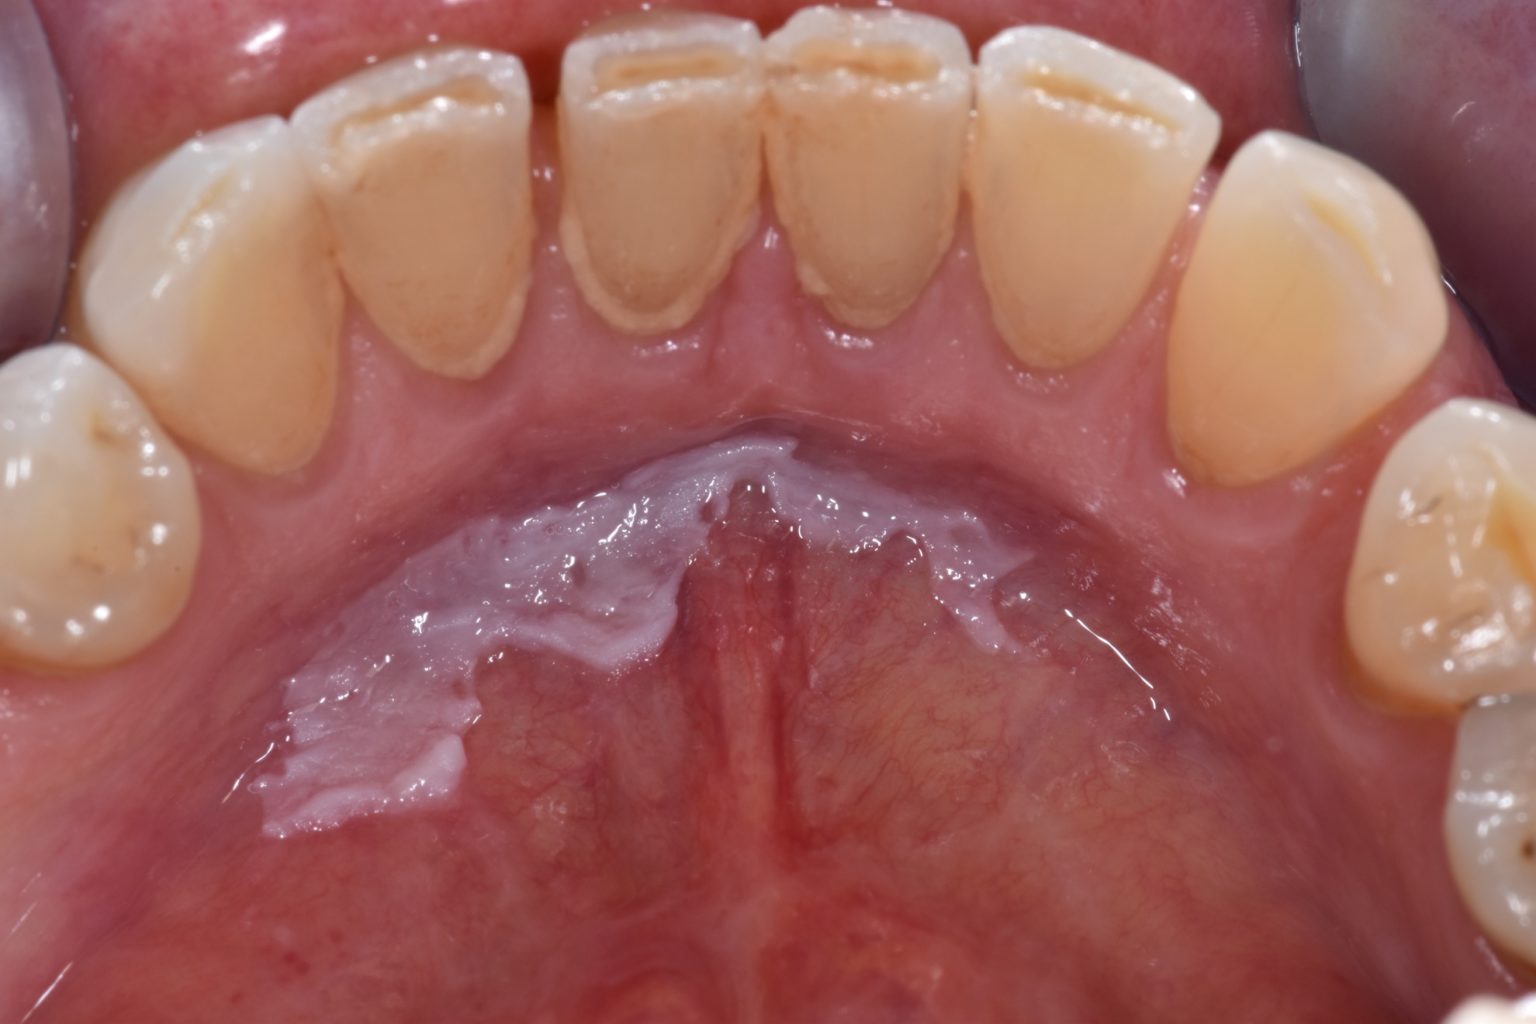

Leukoplakia causes white patches or plaques to develop on the tongue and mucosa in the mouth. Mild leukoplakia is usually harmless and often goes away on its own, but it may be a sign of a more serious condition. Oral leukoplakia is a white patch or plaque that develops in the oral cavity and is strongly associated with smoking. Leukoplakia is a condition that causes painless white or gray patches to develop inside your mouth. The pathogenesis of oral leukoplakia is largely unknown.

Oral leukoplakia is a white patch or plaque that develops in the oral cavity and is strongly associated with smoking. Risk factors include all forms of tobacco use forms,. The patches also may form on the insides of the cheeks and the bottom of the mouth. It is considered an intermediate stage in oral carcinogenesis, driven by multiple somatic genetic.

The patches also may form on the insides of the cheeks and the bottom of the mouth. The pathogenesis of oral leukoplakia is largely unknown. What is leukoplakia, and is it always a symptom of oral cancer? Leukoplakia is a mouth condition involving thick white patches that is most often caused by tobacco use. Leukoplakia causes white patches or plaques.

Leukoplakia Selfcare - The pathogenesis of oral leukoplakia is largely unknown. Discover everything about leukoplakia, its symptoms, causes, and treatments. Leukoplakia causes white patches or plaques to develop on the tongue and mucosa in the mouth. The patches also may form on the insides of the cheeks and the bottom of the mouth. Learn how to manage white patches in the mouth and reduce risks of oral cancer. Leukoplakia is a mouth condition involving thick white patches that is most often caused by tobacco use.